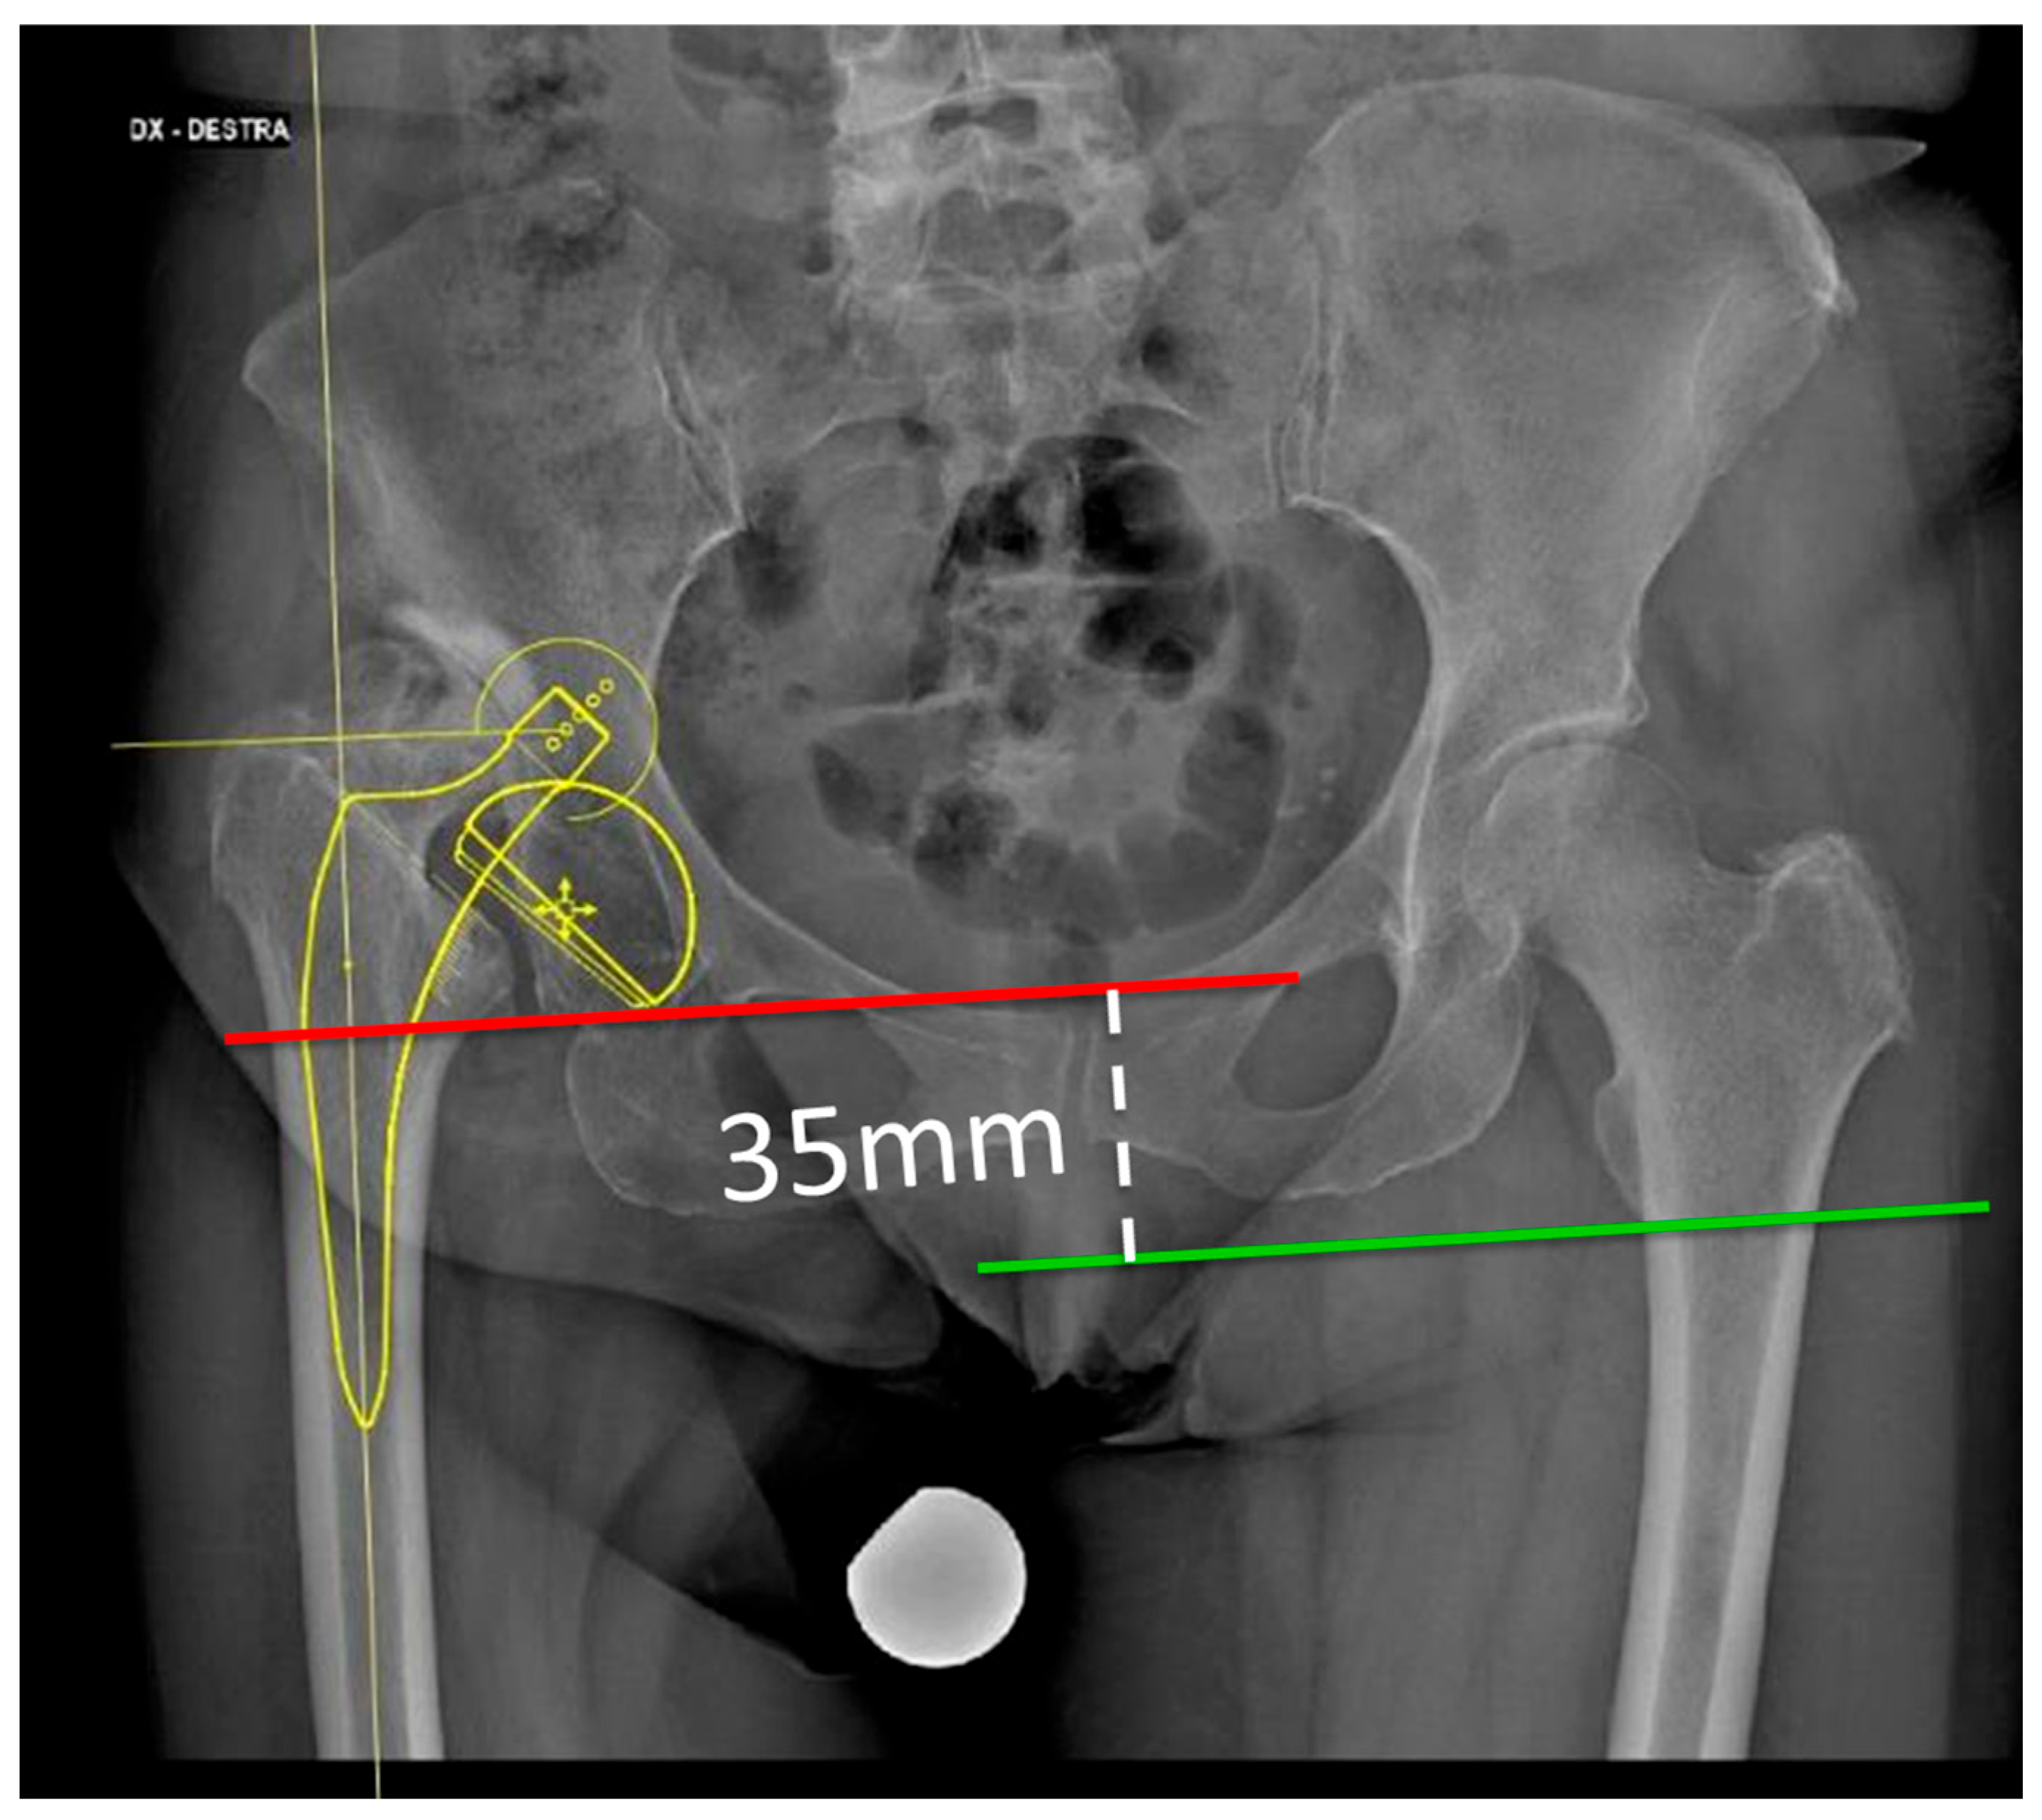

- Limb length discrepancy, either preoperative or after THA surgery, is associated with increased risk of postoperative nerve injury. It is reported that an overall lengthening greater than 3–4 cm after THA increases the risk of nerve injury in the patient by 28%, the damage being caused by traction over the neural structures [33] (Figure 1).